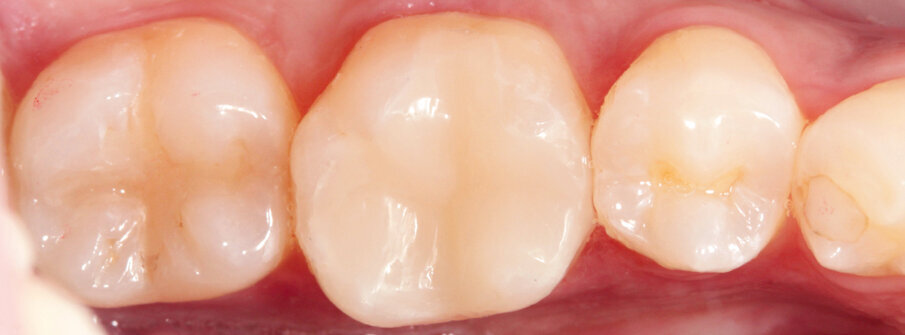

The pre-op showed a defective amalgam filling on tooth 36 in the lower posterior region. The filling needed replacing (Fig. 1). The indication for a multi-surface inlay was given.

Fig. 1: Preoperative situation: defective amalgam filling on tooth 36